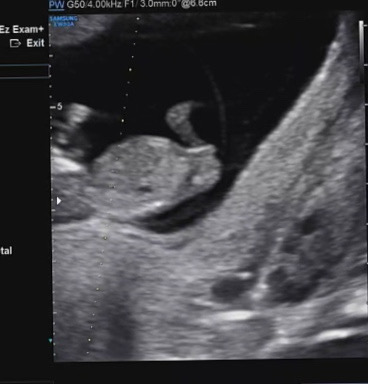

11주 2일 초음파 각도법

아직 이르긴 하지만 딸일까요 아들일까요🙊